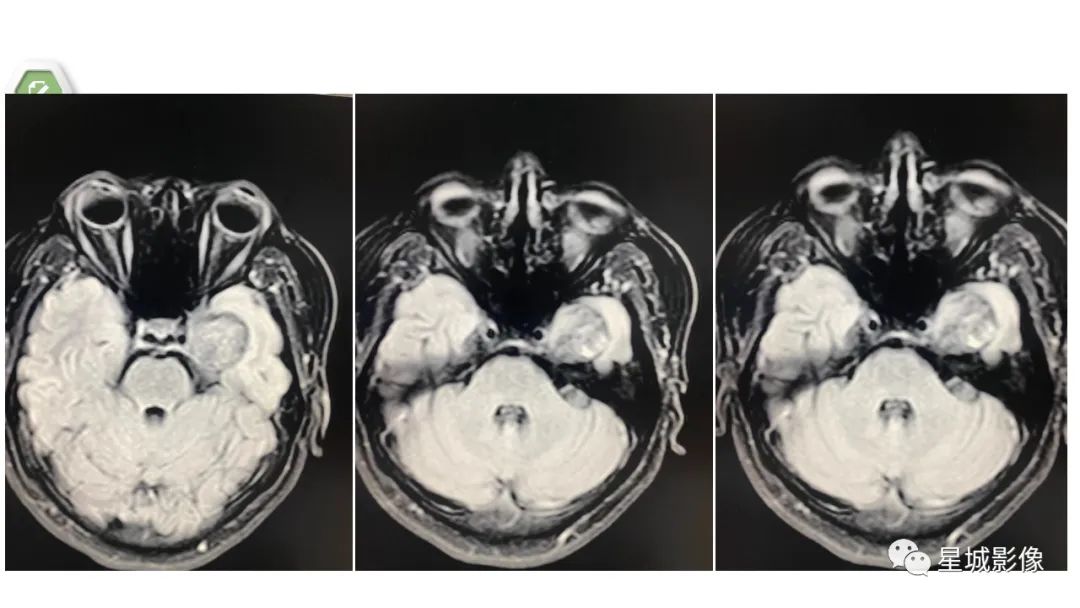

颅内成熟性囊性畸胎瘤1例MR影像表现